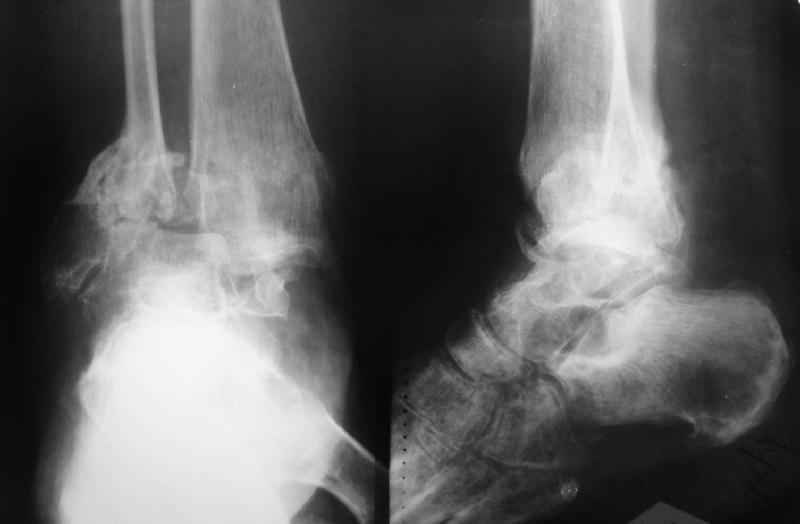

2."Обратите внимание на установку тарана на рентгене! "

В самом деле, снимки некачественные - таран в ротации. Но даже по ним видно, что установка стопы минимум 104 градуса. С одной стороны - В Илизаровской технике пишут, что для женщин допустимо и 110. С другой - почему-то в цивилизованном мире настаивают на четких 90.

А если еще лучше присмотреться, таран в переднем подвывихе, что не кажется допустимым.

Я не совсем понял что за линии на рентгенограмме. Возможно Вы имели в виду это...